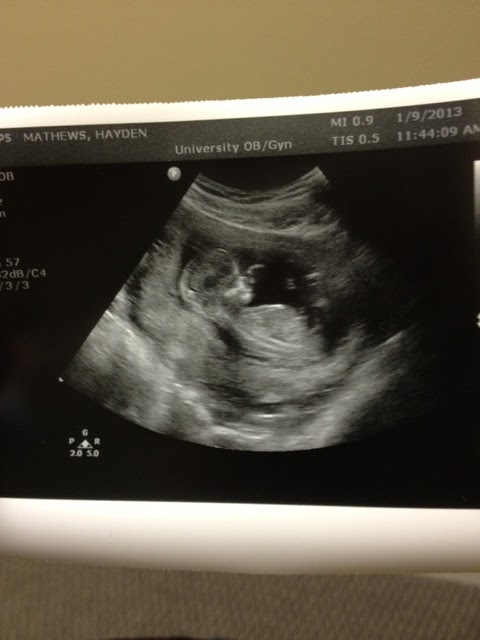

On election day, November 6, was the day I found out I was pregnant.  We had decided about 2 months before that that we were ready to start our family after much prayer and thought.  It seemed like the easiest "Yes".  I was on my lunch break and at home and took a pregnancy test and called Marcus freaking out, we both were so excited and I asked Marcus okay what do we do next?? He replied take two more tests. haha.  I did and of course they were all positive too.  I then called my mom.  We both were so excited.  It was such an amazing day, I should have waited and surprised Marcus with some fancy or cute and creative idea, but the fact that we were going to be parents was just too much for me to hold in! Our baby is due July 16.  We already have a couple names set aside, I think it will be a boy and Marcus thinks a girl.  We find out the gender in 2 weeks.  Unfortunately I have been very sick.  I throw up each day and have been since six weeks. It's been rough working full time, but I just go straight to bed after work and Marcus cleans, cooks, grocery shops, I even tell him what make up to go buy me.  I have had to lean to him for everything.  BYU football just started their work outs and Marcus has to go work out each day at 6AM.  He goes and works out, goes to all his classes(which are all pre-med and extremely hard this semester), goes running with the team, and then comes home and takes care of me.  What a guy.  I never knew I would be this sick, I even had to go get an IV in my arm 2 days ago to get some fluids in me.  Marcus has given me numerous blessings and each one says the same beautiful thing, "Heavenly father is so proud of you, and you will forget all about this sickness when it subsides".  Being this sick has made me so thankful for the healthy body I have.  I never get sick, I'm very healthy and not being able to do the things I want, or taking care of others has been rough... but this is so worth it.  We can not wait for our little baby!  I feel so blessed I was able to get pregnant so quickly.  Here are some pictures from how we announced it, and from the first ultrasound.  PS the doctor I'm using Dr. Judd, he delivered my entire family and when I went to the first visit I asked if he remembered my mom Pam and he said, "Oh yeah and your mom plays tennis and your parents live over by Timpanogos High School, and your dad played football at BYU too.  I can not believe the memory my doctor has! I'm sold on him already! I can't believe the extreme love we already have for this baby.  We constantly talk about him/her and what they will look like, and what their personality will be like.  SO HAPPY! (And Dr. Judd said the sickness should subside by around week 18 hopefully.  I'm already 14 weeks so hopefully it's gone soon! If not, bring it on. )